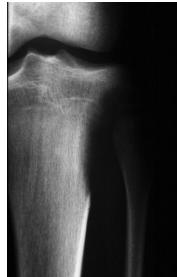

site: distal femur size: Most (involving how much? / cm?) matrix: mixed - mainly radiopaque , wide zone of transition, cortical destruction, resulted periosteal reaction, and codman’s triangle soft tissue involvement: